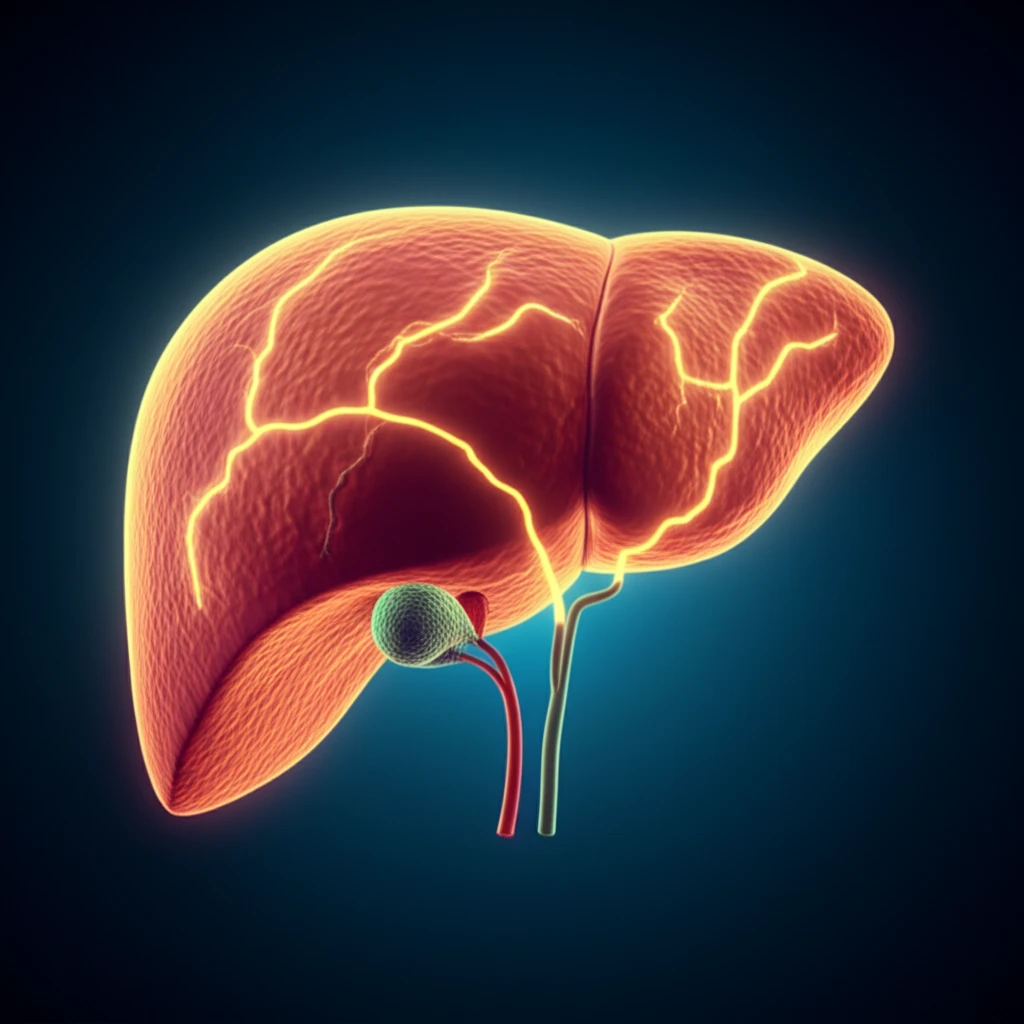

Non-alcoholic fatty liver disease (NAFLD) is a growing health concern, affecting millions worldwide. It occurs when excessive fat accumulates in the liver, leading to inflammation and potential liver damage. NAFLD is often linked to obesity, diabetes, and high cholesterol, making it a significant risk factor for cardiovascular disease and other serious conditions.

The liver's delicate balance between fat storage, breakdown, and export is crucial for overall health. When this balance is disrupted, fat accumulates, leading to NAFLD. Understanding the mechanisms that regulate this balance is essential for developing effective treatments.

Exciting new research has uncovered a key player in liver fat metabolism: an enzyme called Them2. Scientists have discovered that Them2 plays a critical role in directing fatty acids within the liver, influencing whether they are stored, burned for energy, or exported out of the liver. This discovery opens up new possibilities for treating NAFLD and related metabolic disorders.